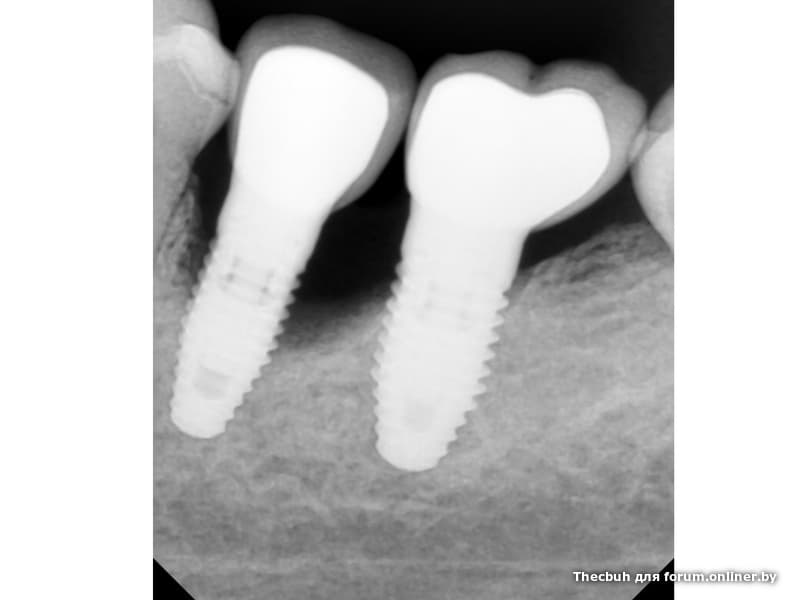

Исследование на рентгене после имплантации зубов

Раздел: Снимки-откровения